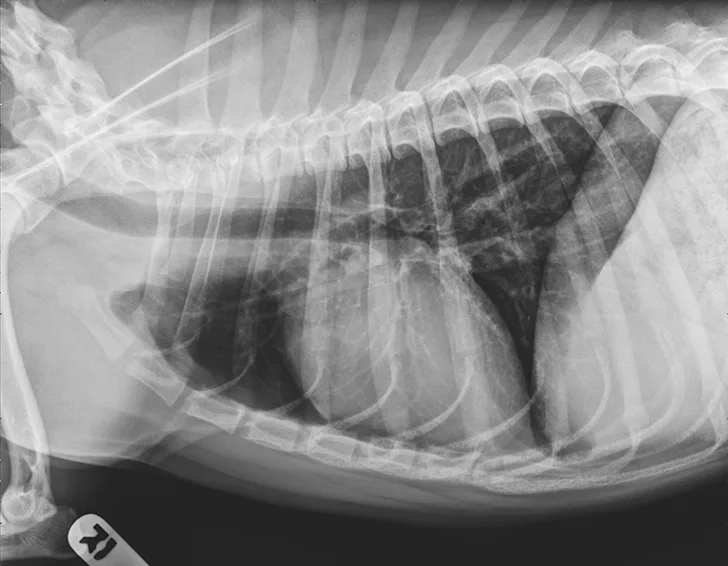

Thoracic radiographs revealed a moderate, diffuse, bronchointerstitial pattern (Figure 1). The cardiac silhouette, pulmonary vasculature, and extrathoracic structures were normal. Airway sampling via bronchoscopy was recommended based on radiographic findings. CBC and serum chemistry profile were performed prior to sedation. Serum chemistry results were within normal limits. CBC revealed leukocytosis (24.3 x 103/µL; normal range, 4.9-17.6 x 103/µL) characterized by marked eosinophilia (10.4 x 103/µL; normal range, 0.07-1.49 x 103/µL), monocytosis (1.4 x 103/µL; normal range, 0.13-1.15 x 103/µL), and band neutrophilia (729/µL; normal range, 0-170/µL). Heartworm antigen test was negative.

Thoracic radiographs are generally characterized by a diffuse bronchointerstitial pattern with peribronchial cuffing and thickening of the bronchial walls. In some cases, bronchiectasis or alveolar infiltration may be observed.2,6-8 Occasionally, patchy pulmonary opacities create a nodular appearance.4 Radiography is critical for ruling out other common causes of cough and/or acute respiratory distress. Concurrent disease processes (eg, cardiomegaly, tracheal collapse) can complicate diagnosis.